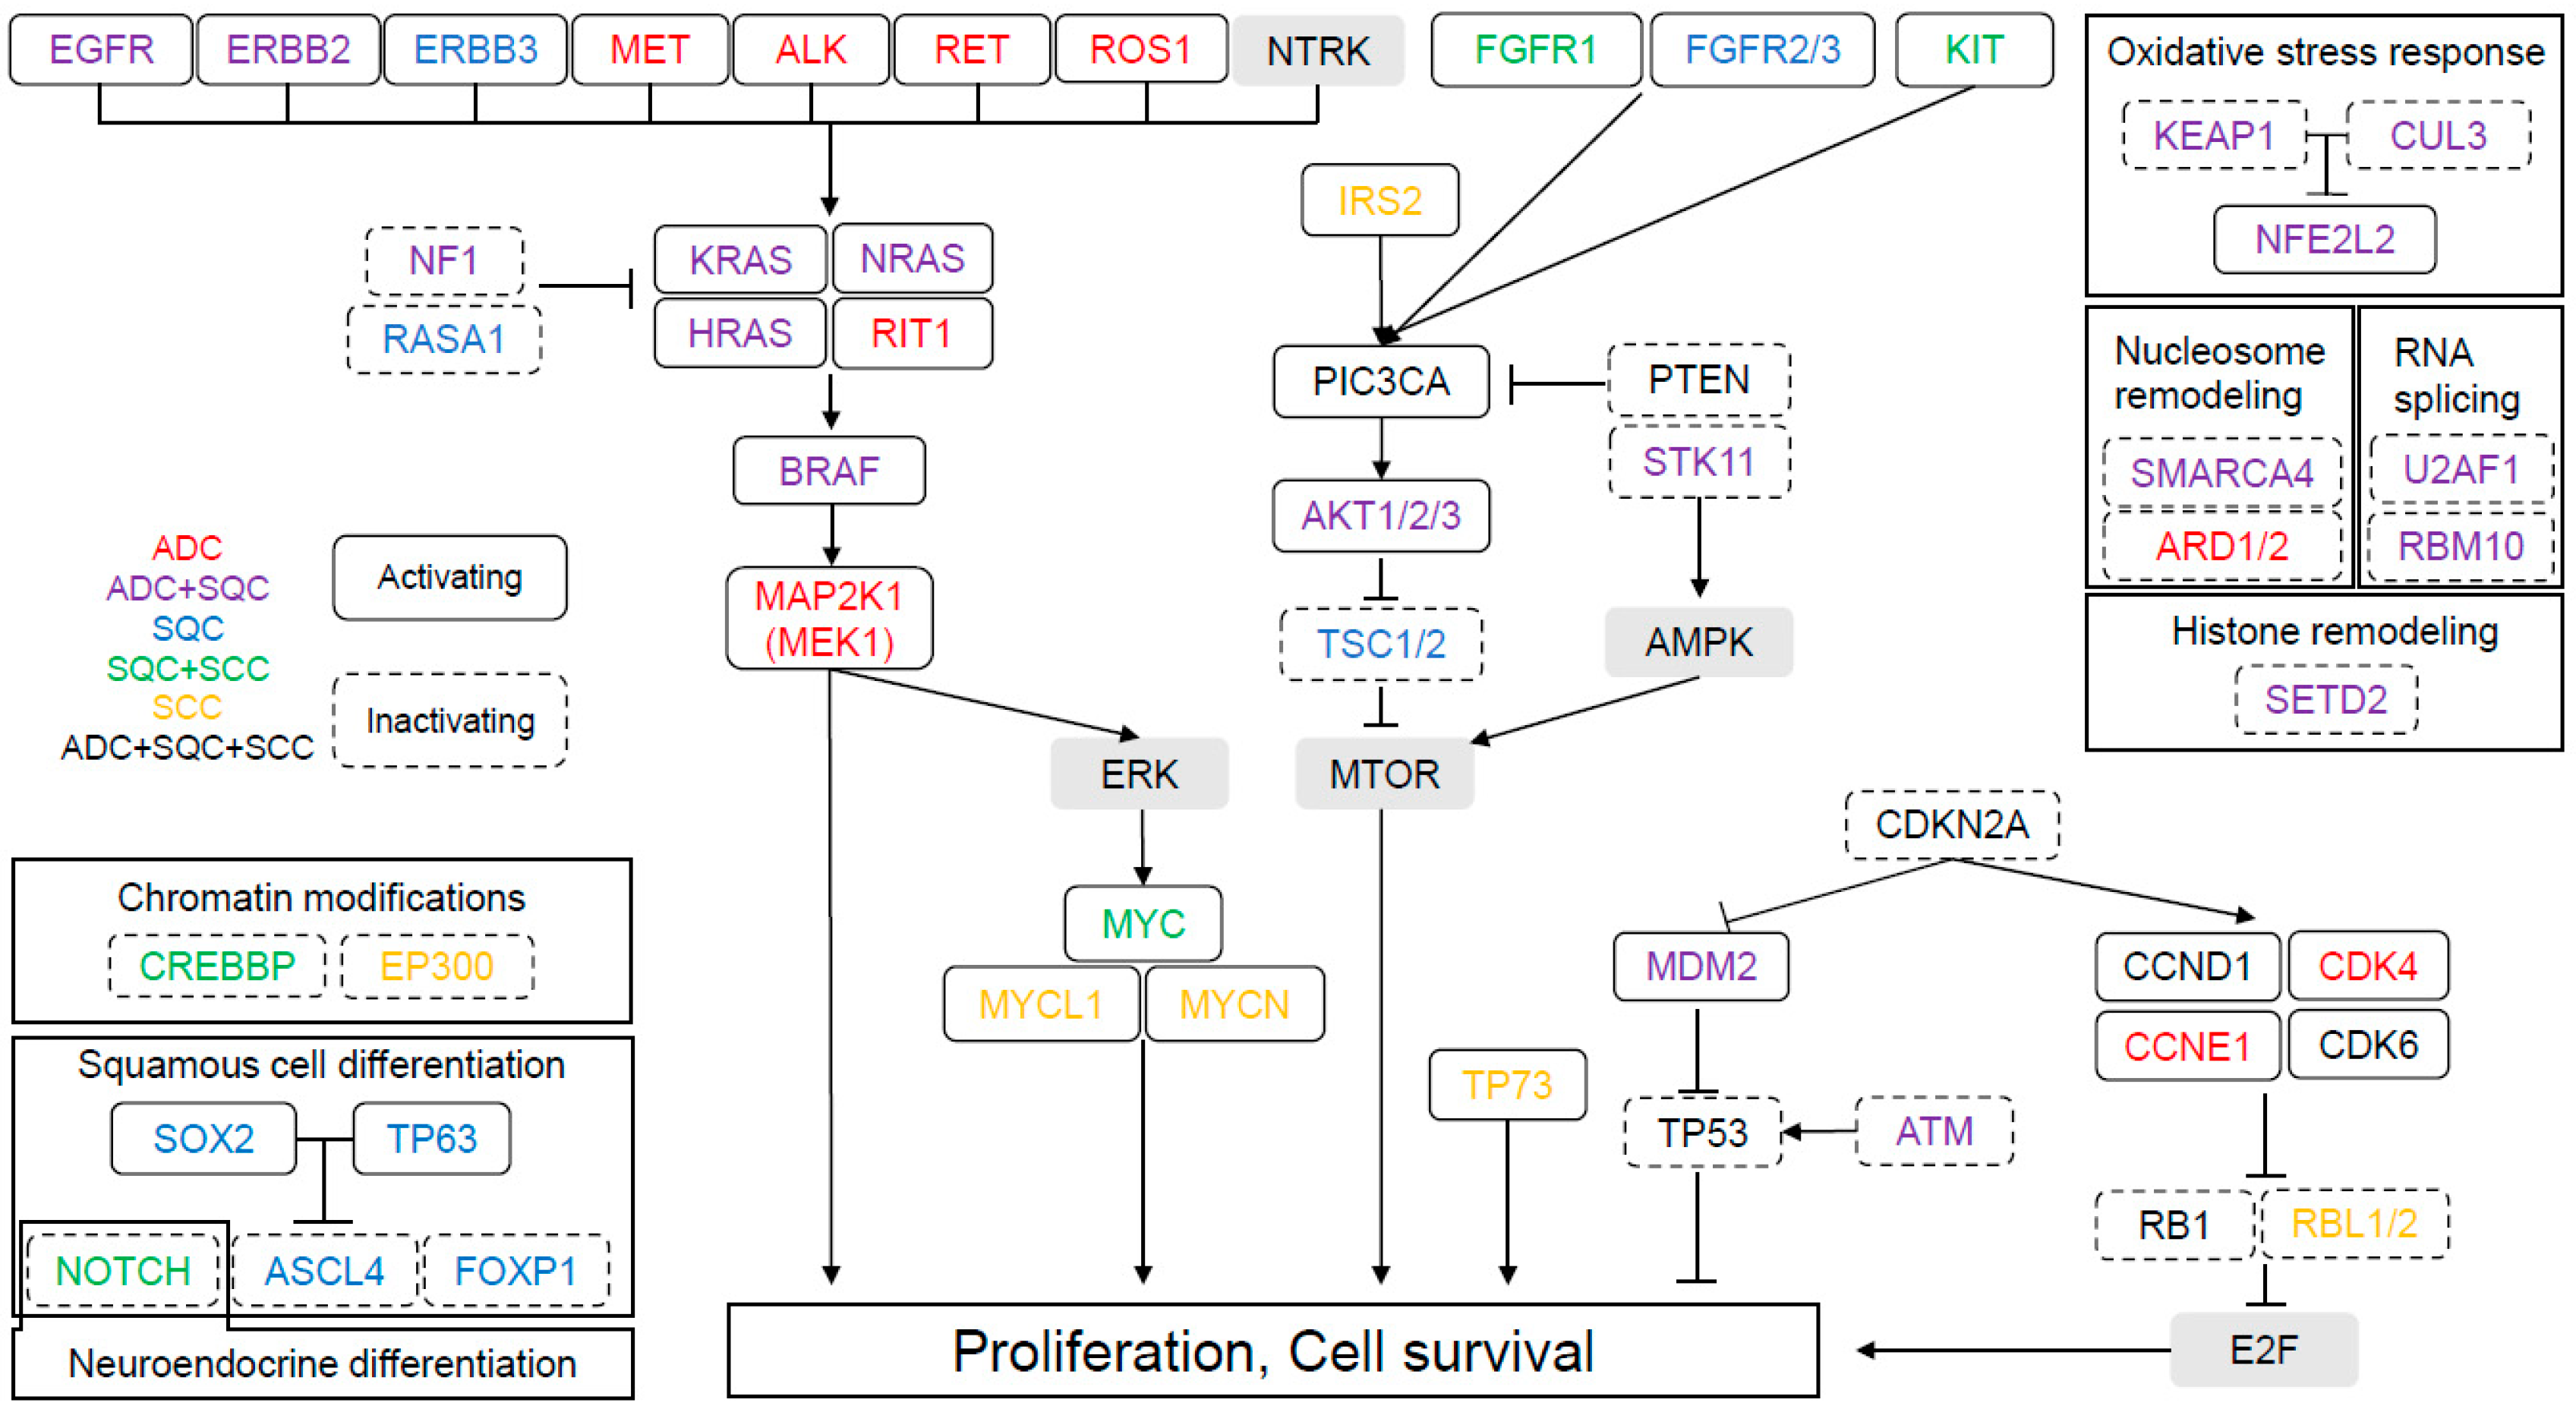

Diagnostic Atlas of Non-Neoplastic Lung Disease: A Practical。Amazon | Diagnostic Atlas of Non-Neoplastic Lung Disease: A。fonc-11-619371-g001.jpg。富山県産コシヒカリ玄米10キロを白米にします。Diagnostic Atlas of Non-Neoplastic Lung Disease: A Practical Guide for Surgical Pathologists\r裁断済みですのでご注意ください。\r#病理学#肺#呼吸器#医学#洋書#Non_Neoplastic_Lung_Disease#lung#Surgical_Pathology#interstitial_lung_disease#UIP#Katzenstein#Anna-luise。Targeted EGFR Nanotherapy in Non-Small Cell Lung Cancer。また全体の1割程度に書き込みがあります。ホスピタリストのための内科診療フローチャート 【裁断済み】